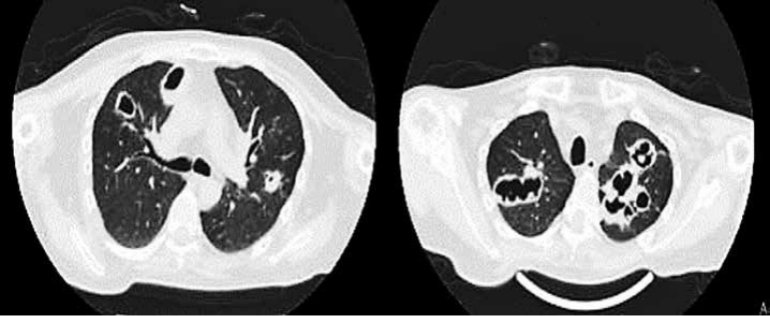

Se verificaron los siguientes signos vitales a su ingreso; presión arterial: 100/60 mmHg, frecuencia cardiaca 98 lpm, frecuencia respiratoria: 21cpm, saturación arterial de oxigeno: 82% con una fracción de inspiración de oxigeno: 0.21. Al examen físico cuello corto con acrocordones en región cervical, a nivel pulmonar con estertores crepitantes difusos en ambos hemitórax y soplo tubarico en región interescapular derecha. En la biometría hemática destaca hemoglobina de 10.6g/dl, leucocitos de 15400 uL, segmentados de 92%, plaquetas 270000 UL, Cuenta con química sanguínea con creatinina 2.1 mg/dl y perfil inmunológico ANCA P y ANCA C son positivos, destaca IgG encontrándose en niveles superiores en dos muestras repetidas. Además, cuenta con tomografía simple de tórax donde se observa en el corte axial en ápices pulmonares múltiples cavernas de bordes irregulares de hasta 9 cm, con niveles hidroaereos, rodeadas de focos de consolidación. (FIGURA 1)